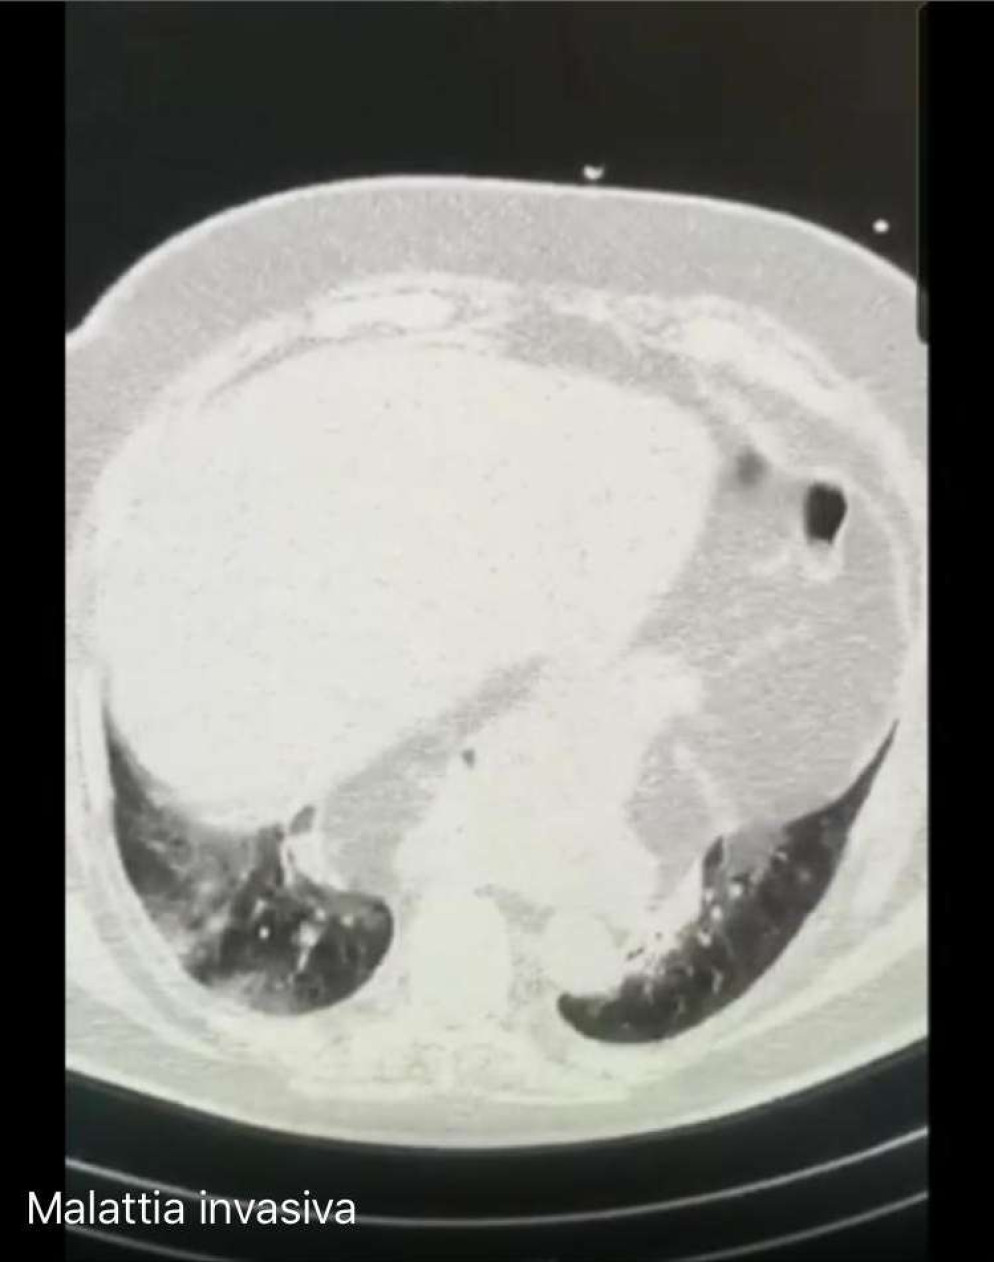

Nella foto “malattia invasiva”, invece, è l’andamento della malattia più invasiva. Le parti più chiare sono quelle relative al coronavirus che, avanzando, occupa sempre più spazio all’interno dei polmoni. In questo caso la polmonite si trova già in stato avanzato provocando l’insufficienza respiratoria. I medici hanno riscontrato che il Covid può occupare anche i vasi polmonari.